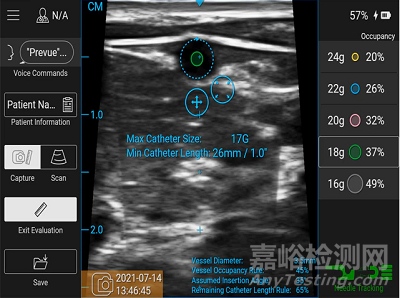

BD Prevue™ II血管接入系統(tǒng)具有創(chuàng)新的血管評(píng)估工具,可幫助臨床醫(yī)生根據(jù)插入位置和角度選擇合適的導(dǎo)管長(zhǎng)度和規(guī)格,以便他們每次都能做出明智的決定。

其評(píng)估工具可以幫助臨床醫(yī)生根據(jù)血管使用率、血管長(zhǎng)度和注射的插入角度選擇合適的靜脈進(jìn)行穿刺;而可調(diào)的吊桿臂可在超聲波屏幕下方調(diào)整到患者手臂的高度,以便達(dá)到在放置靜脈注射裝置時(shí)形成清晰的視線。